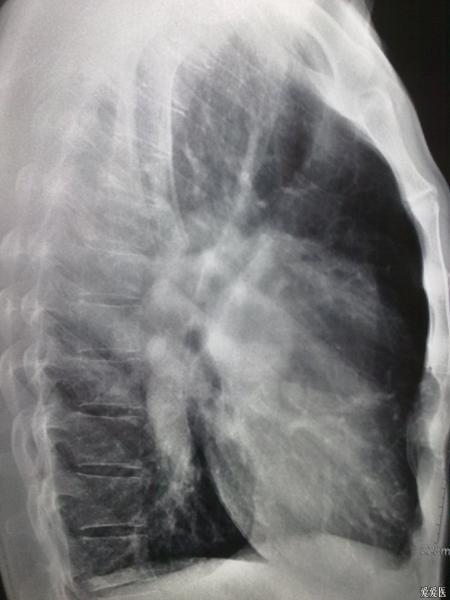

典型肺动脉高压胸片(室间隔缺损)

1、肺动脉段突出。2、肺血管纹理变少了。3、右心室大,心尖圆钝。。